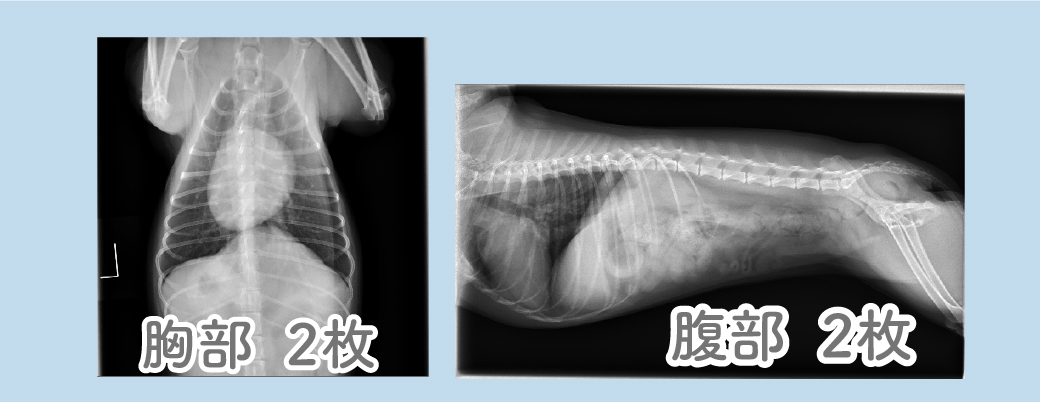

《レントゲン検査》

骨や心臓、肝臓などの臓器の形状に異常がないかや、他にもカルシウム沈着などを確認できます。

腎臓などに結石がある場合などの発見にも役立ちます。